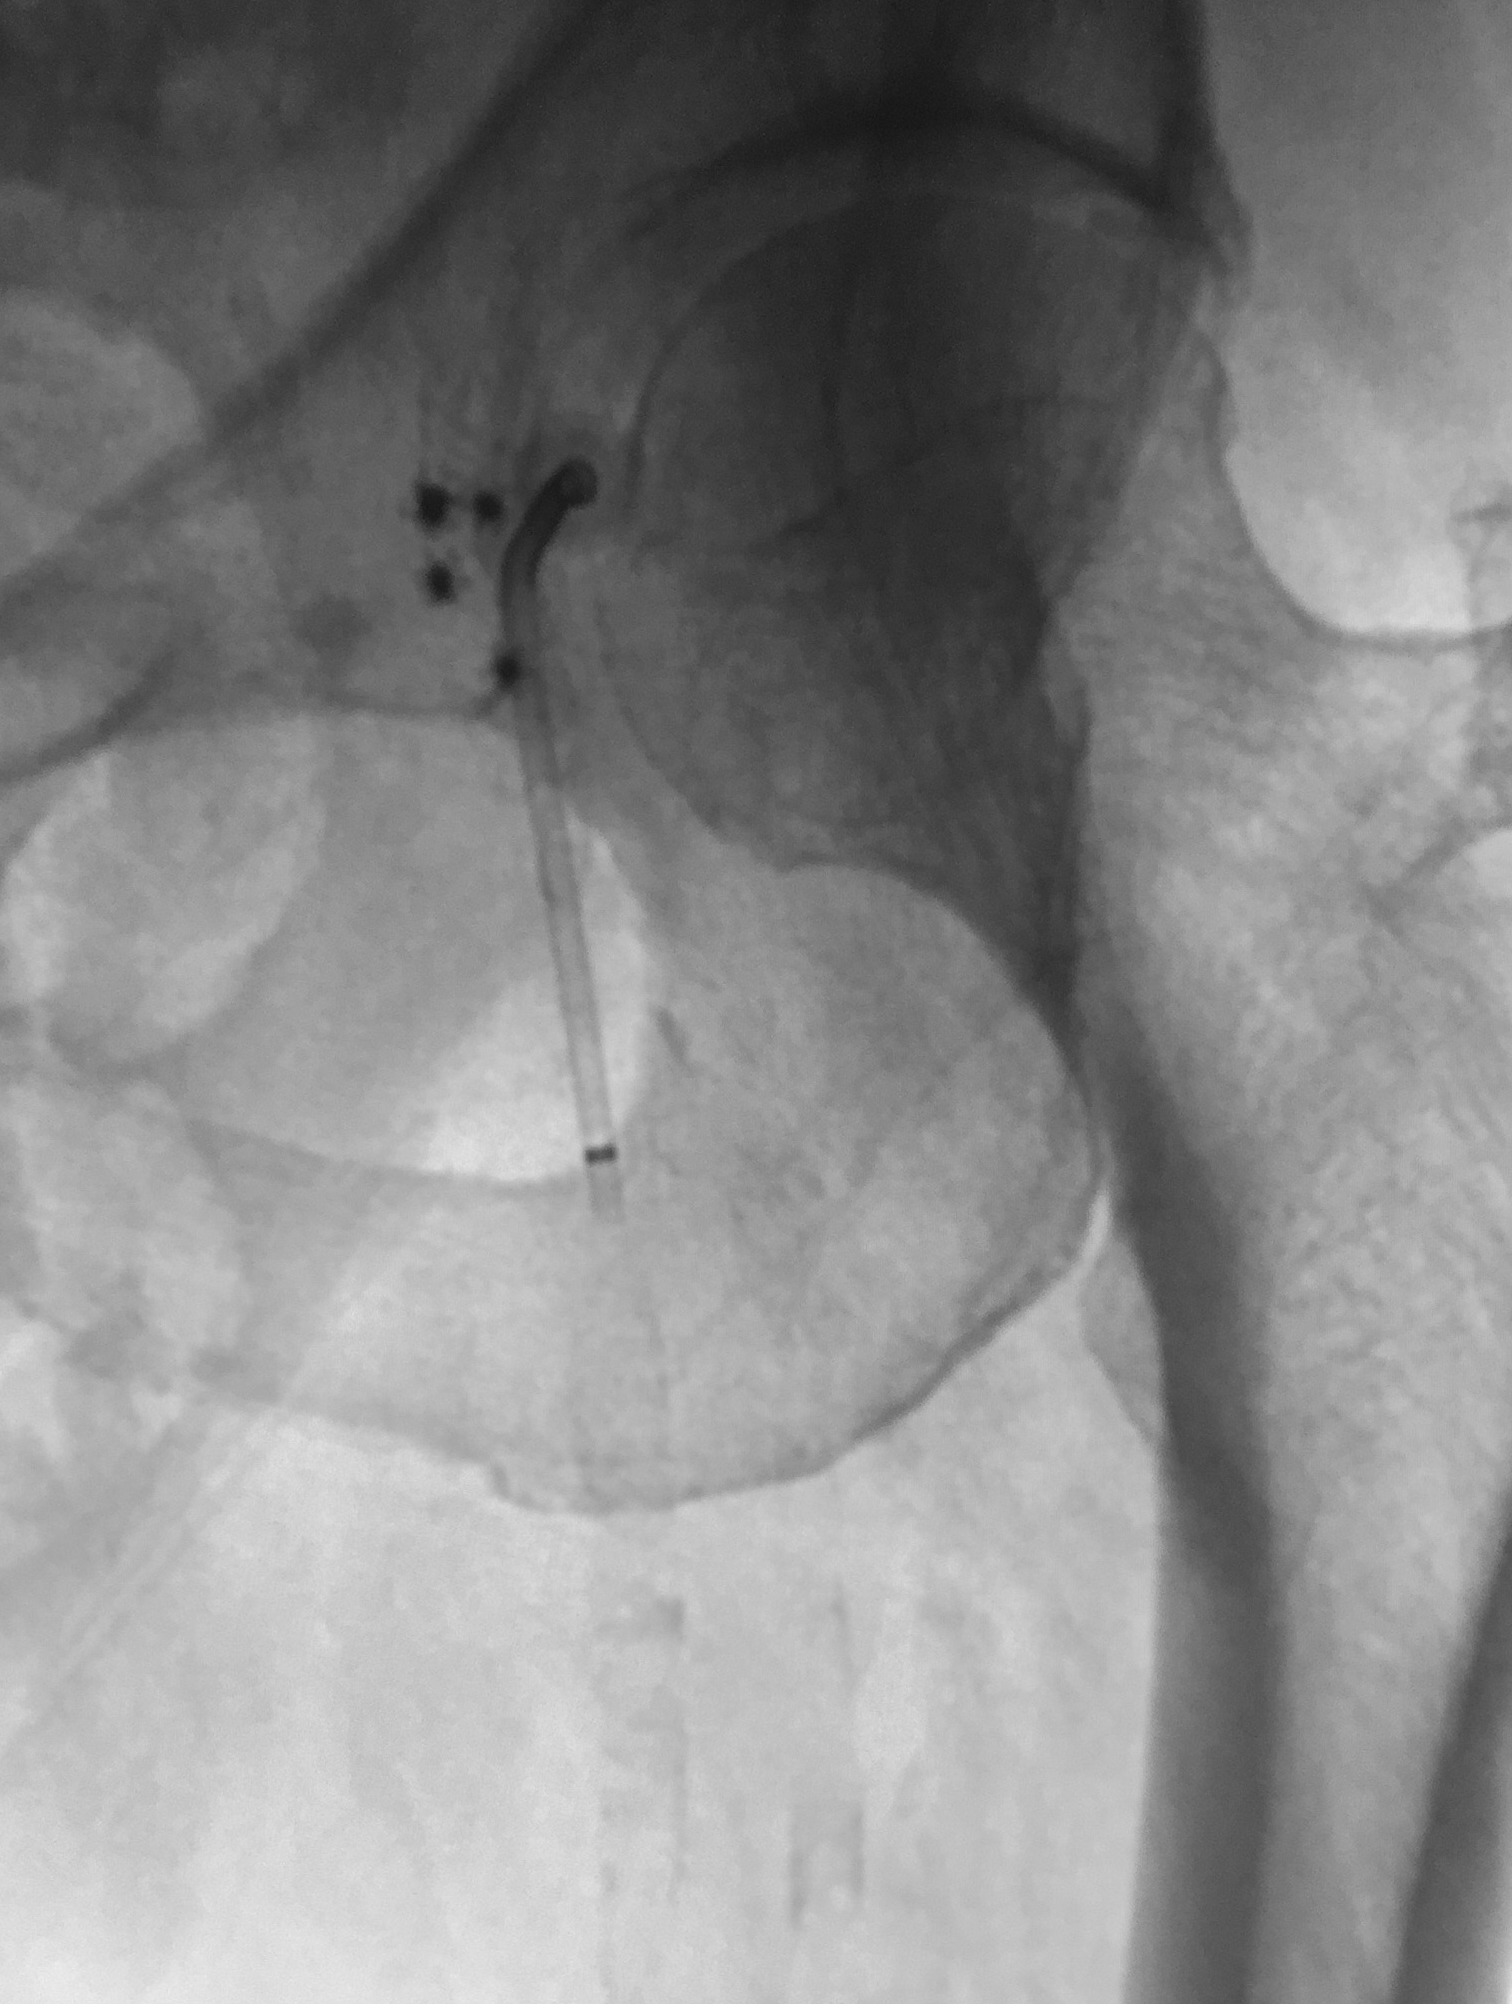

Two previously deployed Celt ACDs (indicated by arrows above) in a vessel with an inflated Scoring Balloon for angioplasty of femoral stent.

Ante-grade puncture in calcified vessel previously closed by Celt ACDs following multiple procedures.